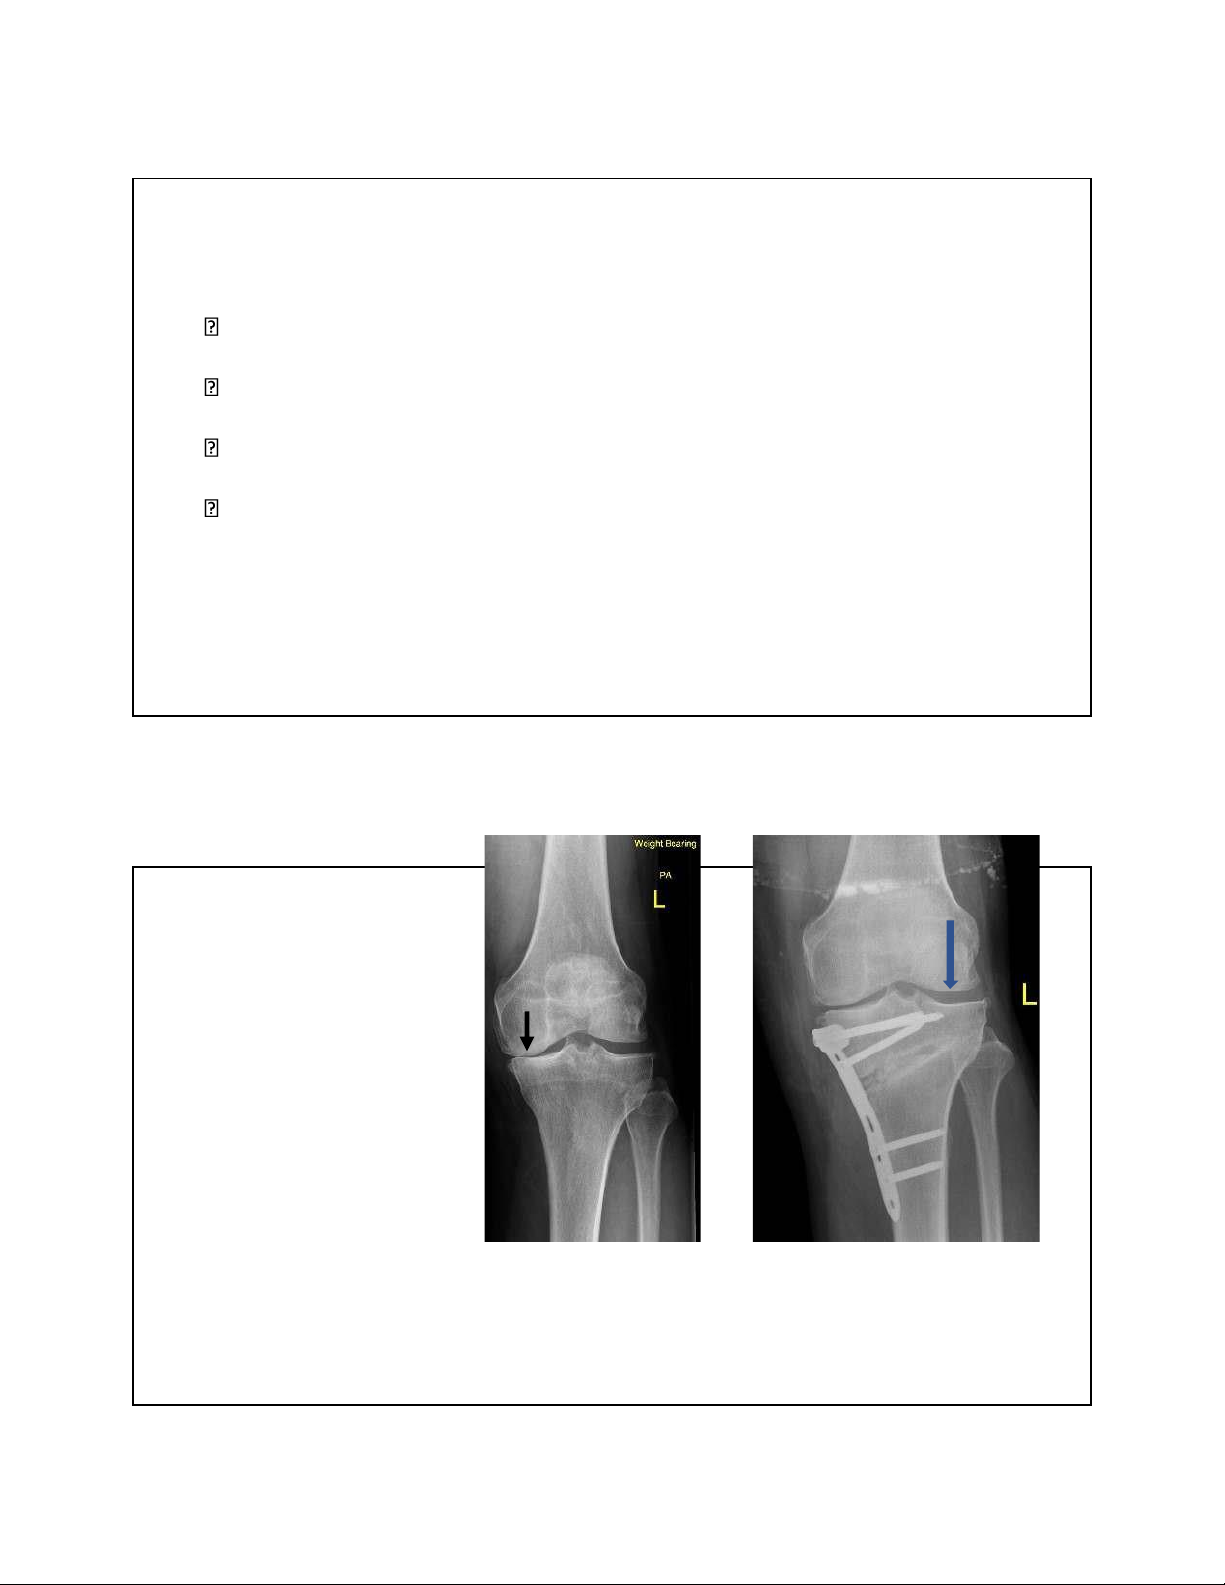

CẮT XƯƠNG SỬA TRỤC (HTO: high tibial osteotomy)

• Được thực hiện vào những năm 1950 - 1960

• Chỉ ịnh cho thoái hoá 1 khoang: khoang trong hoặc ngoài của khớp gối

• Gối varus(vẹo trong) hay valgus(vẹo ngoài)

• Bị giảm vai trò sau này do sự phát triển và thành công của thay khớp

• Nhược iểm: kết quả không hằng ịnh do chậm chịu lực, khớp giả, liệt

thần kinh mác…kết quả giảm dần theo thời gian

• Có tác dụng kéo dài ặc biệt là BN còn trẻ 27 CẮT XƯƠNG SỬA TRỤC

• Mục ích: chuyển lực từ khoang bị thoái hoá sang khoang lành

• Chậm tiến trình thoái hoá, giảm au

• Làm chậm quá trình thay khớp Chọn bệnh • <60t

• Khớp chè ùi còn tốt??? • Thoái hoá 1 khoang???

• Gối vững ( dây chằng còn nguyên vẹn) 28 lOMoAR cPSD| 22014077 7/15/2023 Cắt xương sửa trục Chống chỉ ịnh: >60 tuổi Béo phì Hư 2-3 khoang

Vẹo trong(varus) trước và sau cắt xương 30 lOMoAR cPSD| 22014077 7/15/2023 Bn nữ 58t, gãy mâm chày 14th • Thay khớp hay bảo tồn khớp? 31 Chân vẹo trong sau mổ KHX 32 lOMoAR cPSD| 22014077 7/15/2023 33 lOMoAR cPSD| 22014077 7/15/2023 1 năm sau mổ 34 Dáng